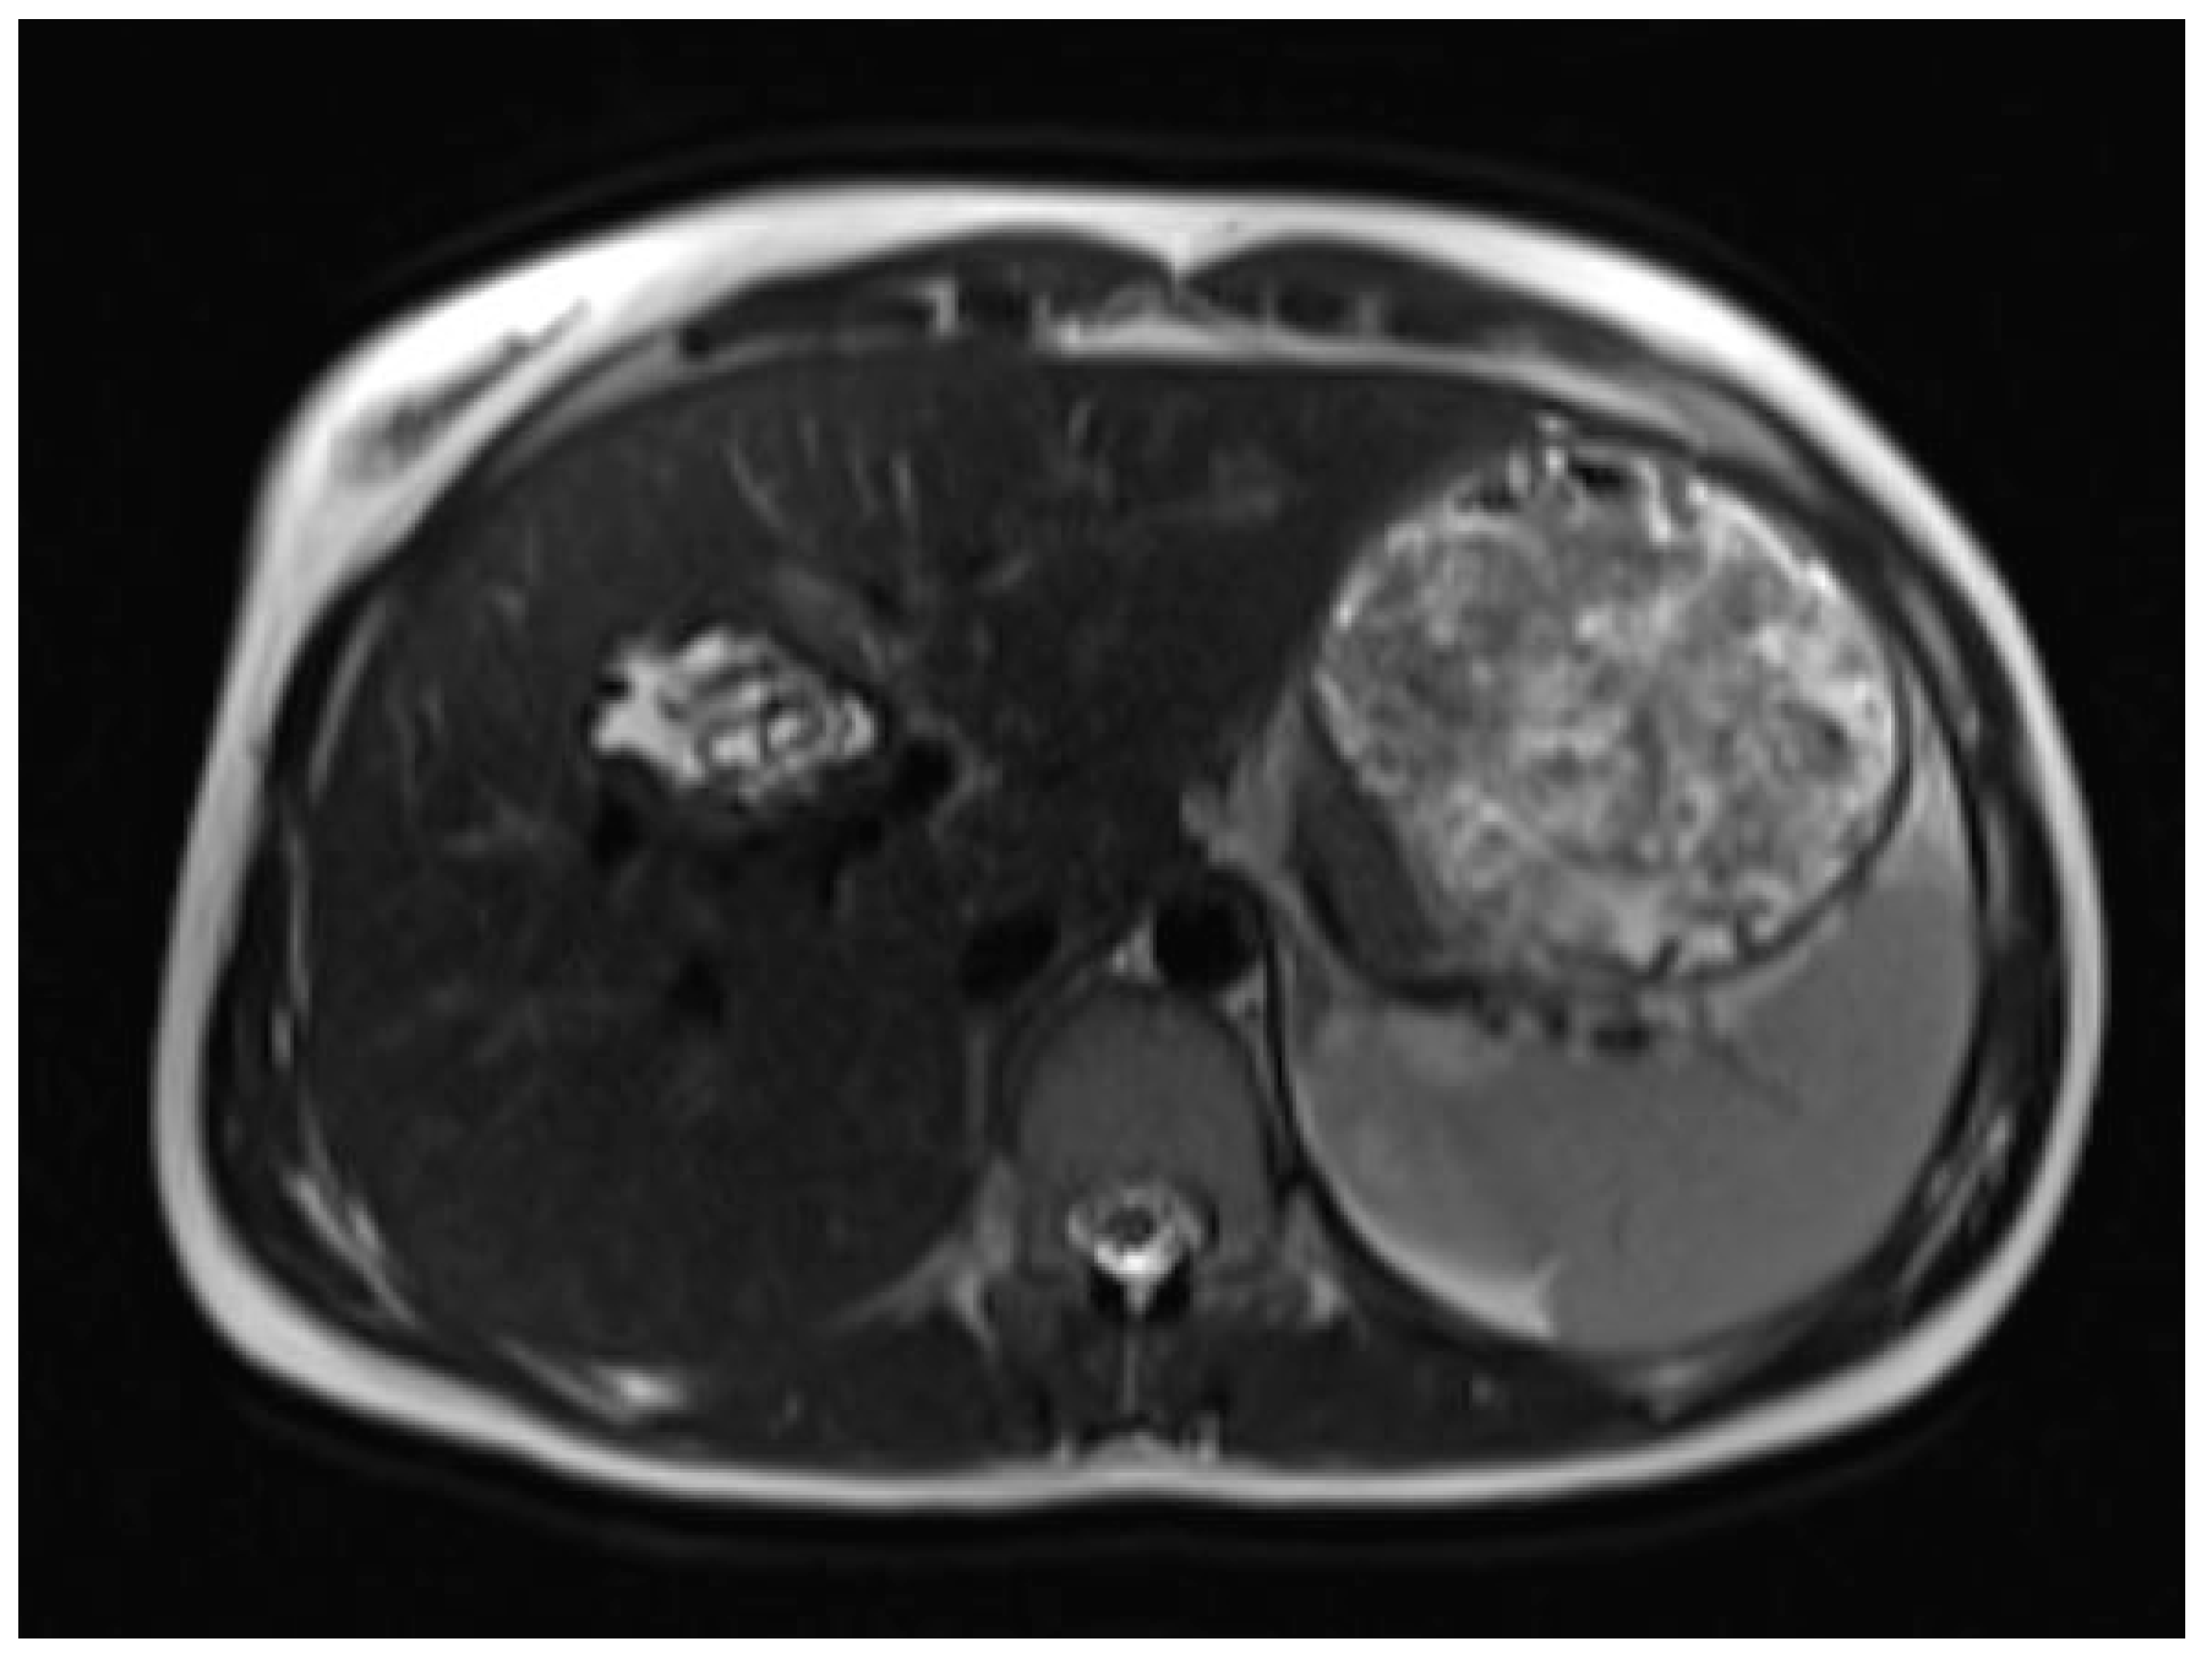

A liver MRI scan confirmed a cystic structure with multiple daughter cysts, hypointense on a T1-weighted image (T1WI), and hyperintense on a T2-weighted image (T2WI), with no solid components, no signs of membrane rupture, and a maximum diameter of 10 cm (craniocaudal) (Figure 1). Additionally, elevated signals on T2WI in the surrounding liver tissue were found. The T1 sequences did not reveal any contrast uptake after 5 (Figure 2), 10, or 20 (Figure 3) minutes post-injection. Furthermore, DWI/ADC mapping indicated a hydatid cyst. The DWI sequences included a trace DWI (Figure 4), an ADC map (Figure 5), and both at b800. Radiomics and AI tools were not involved. The trace DWI showed an area of hypointensity in the region of the cyst that was surrounded by a hypointense layer, depicting the cystic wall. The ADC map revealed hyperintensity within the area, in concordance with a typical depiction of cysts on an MRI scan.

Figure 1.

First MRI scan: Axial T2W MRI scan revealing hyperintense areas in liver segment IV, suspicious daughter cysts, and clearly visible septation.

MR imaging clearly visualizes pericyst, matrix, and daughter cysts. The pericyst appears as a hypointense rim on both T1WI and T2WI due to its fibrous structure and the presence of calcifications. This is a specific feature of hydatid cysts, called the rim sign, mostly better visualized on T2WI [5]. The matrix represents hydatid-fluid-containing membranes of broken daughter vesicles, scolices, and hydatid sand [7]. The hydatid matrix appears hypointense on T1WI and significantly hyperintense on T2WI. However, the limitations of MRI scans are especially observed in stages CE4–CE5, as bigger calcifications are better observed on a CT scan. When daughter cysts are present, they are typically more hypointense than the matrix on T2WI, as observed in our case report [17] (Figure 1). If the membrane is separated, it can shift with movement, resembling a water lily floating on the surface of a pond, previously described as water-lily sign, which was seen in our case report as well [18] (Figure 8).